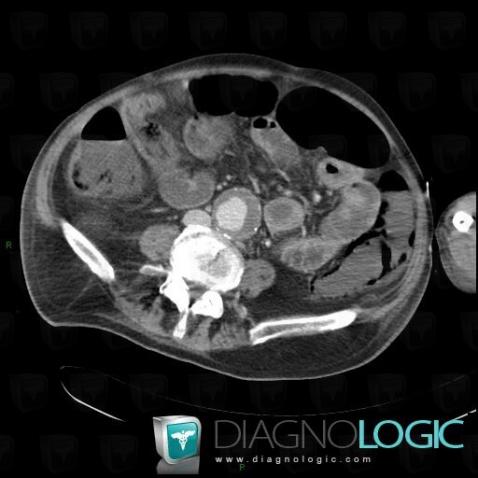

Ischemic colitis, Colon, CT

Here is the specific information in the key image above:

- Diagnosis Ischemic colitis, Location(s) Colon, with gamuts Thickening of colon wall